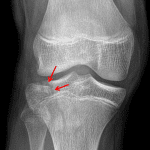

Age: 11

Sex: Female

Indication: Knee injury

Sample ReportAcute minimally depressed Salter IV fracture of the lateral tibial plateau. No physeal widening.

Large joint effusion.

No joint malalignment.